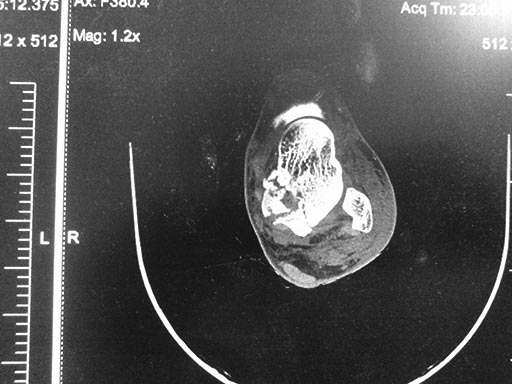

Выявлено: Оскольчатый перелом таранной кости со смещением в

таранно-пяточном сочленением, без смещения в голеностопном суставе.

Наложена гипсовая иммобилизация.

Неделю получал консервативное лечение, отек умеренный, не напряженный, в

большей мере спал, пузырей нет. Сегодня выполнена контрольная

рентгенография. Вопросы: Имеется ли импакция костной ткани тарана?

Сохраняется подтаранный подвывих? Какой вариант лечения предложили бы

вы(консервативный, оперативный)? Если рассматривать возможный вариант

оперативного лечения, мое мнение - предпочтительна дистракция и фиксация

в полноценном аппарате внешней фиксации. А может быть "не трогать", и

лечить консервативно? Буду признателен за советы, парень молодой,

необходимо получить хорошую функцию.